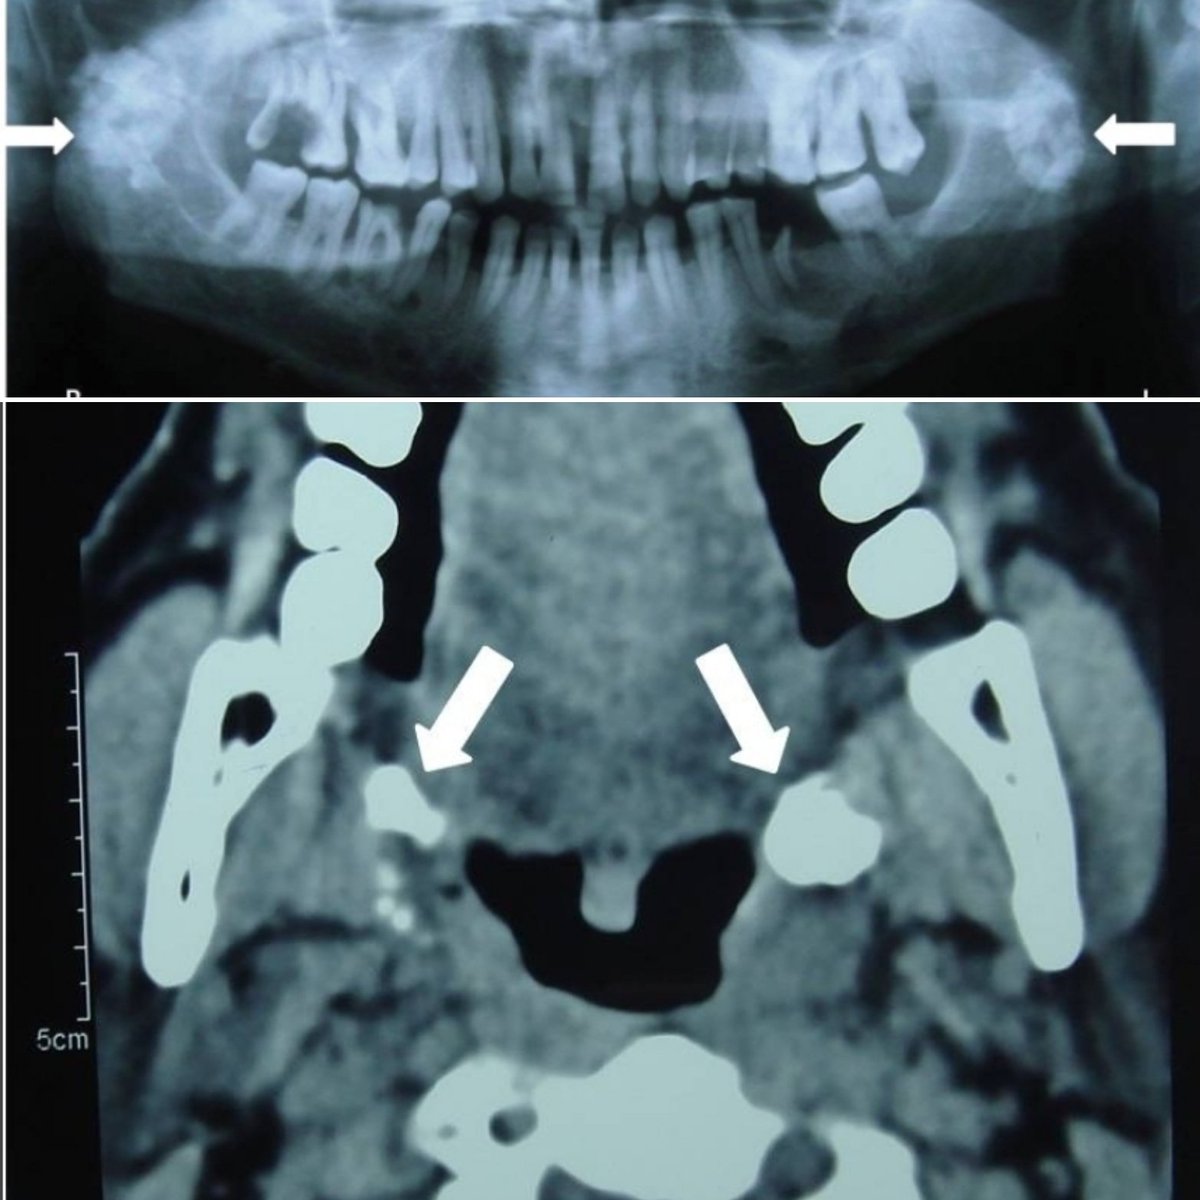

وفي حالات "وقد تكون نادرة أيضا"، تتكون حصوات في هذه اللوز،

وأيضا قد لا تشكل أي عرض، مثال: أُخِذت الأشعة في الصورة لمريض يعاني من مشكلة متعلقة بالفك وليس لها علاقة أبدا باللوز ولكن صدف أن تم ملاحظتها في الأشعة ولم يعمل للوزتي المريض أي إجراء.